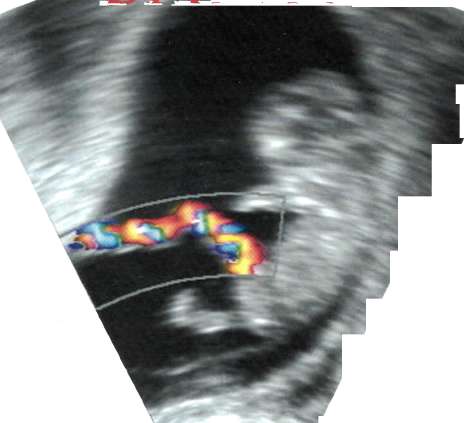

Kordon kanı naklindeki en önemli unsurlardan biri, doku (HLA) uyumu. HLA antijenleri (Human Leucocyte Antigen-İnsan Lökosit Antijeni), doku uygunluk antijenleri olarak tanımlanan, vücudun kendi hücreleri ile yabancı hücreleri birbirinden ayırt etmesine yarayan moleküller. HLA bölgeleri, nakil için alıcı ve verici arasındaki doku uyumunu belirliyor. HLA uyumu tam olmadığı durumlarda, dokular karşılıklı birbirlerini reddediyor ve nakil başarısız oluyor. Bazen de, nakledilen doku hastanın vücudunu düşman olarak görüyor ve ona karşı savaş açarak GVH (Graft Versus Hoşt) hastalığına neden oluyor. Verici hücrelerinin alıcı hücrelerine karşı geliştirdiği bu reaksiyon daha çok karaciğer, cilt, mukoza, sindirim sistemi hücrelerine karşı gelişiyor ve iki yıl içinde hastaların %50'sinde ortaya çıkıyor. Kordon kanı kök hücre nakillerinde, hücrelerin antijenik yapısı henüz tam geliş-

memiş olduğundan bu oran çok daha düşük.

Sonuç olarak vericiyle hastanın HLA antijenlerinin birbirine uyumu ne kadar yüksekse naklin başarı olasılığı o kadar yükseliyor. HLA antijen uyumu aile içinde % 30- 40 gibi yüksek olasılıklara ulaşabiliyor. Aile dışında bir kişiden doku uyumuysa çok düşük bir olasılık. HLA antijenlerine özel kan testleriyle bakılıyor ve nakil için en az 5 antijenin uyumlu olması şartı aranıyor. Kordon kanı naklinin başarısı alıcıya uyumlu kök hücrenin yanısıra bu hücrelerin miktarına da bağlı.